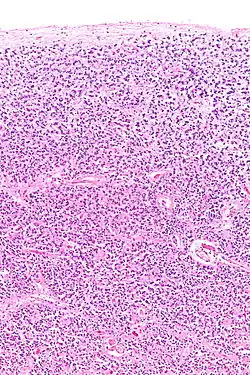

Micrograph of a normal pineal gland – very high magnification

The pineal body in humans consists of a lobular parenchyma of pinealocytes surrounded by connective tissue spaces. The gland's surface is covered by a pial capsule.

The pineal gland consists mainly of pinealocytes, but four other cell types have been identified. As it is quite cellular (in relation to the cortex and white matter), it may be mistaken for a neoplasm.[18]